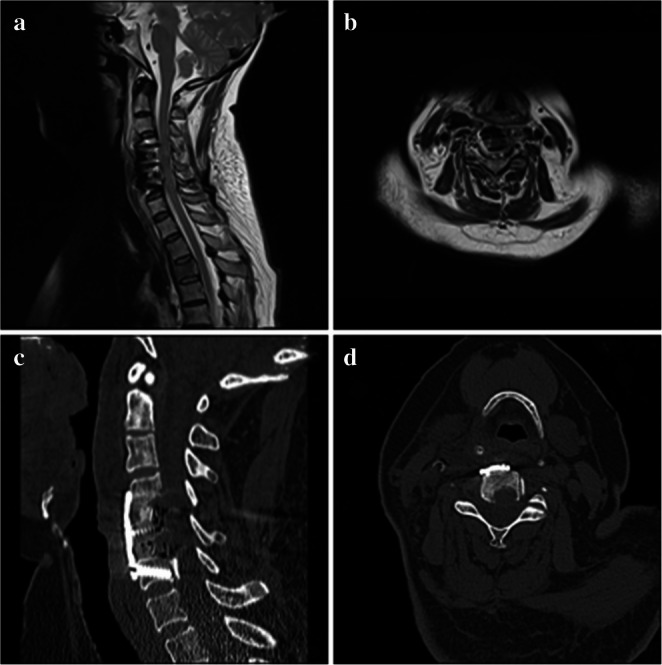

Cervical ossification of the posterior longitudinal ligament (OPLL) causes spinal cord compression due to spinal canal stenosis. Traditional anterior approaches such as anterior cervical discectomy and fusion (ACDF) and anterior cervical corpectomy and fusion (ACCF) have limitations, including restricted decompression range, extensive vertebral resection trauma, or insufficient stability. This study aimed to evaluate the efficacy and safety of a novel surgical technique-Anterior Cervical V-Slot Decompression and Fusion (ACVDF)-for treating long-segment OPLL. A retrospective analysis was conducted on 30 patients with multilevel OPLL who underwent ACVDF between December 2021 and March 2024. A curved grinding drill was used to precisely remove portion of the vertebral body and ossified tissue (≤ 50% of the sagittal diameter) through the V-shaped distracted intervertebral space, achieving direct decompression of long-segment OPLL During surgery. Postoperative follow-up 14.70 ± 1.62 months (12-18 months). Clinical outcomes were assessed using the Japanese Orthopaedic Association (JOA) score, visual analog scale (VAS) score, and imaging methods such as CT and MRI. All 30 patients successfully completed the surgery, with a mean operative time of 143.17 ± 10.96 min and intraoperative blood loss of 177.67 ± 49.45 ml. At the final follow-up, the JOA score improved from 8.50 ± 1.96 to 14.67 ± 0.71 (P < 0.05), with an excellent and good rate of 90.00%. The VAS score decreased from 6.53 ± 1.53 to 1.30 ± 0.79 (P < 0.05). The spinal canal occupancy rate decreased from 42.13 to 10.61% (P < 0.05). The Height of the fused segments was 62.70 ± 13.58 mm at 1 week postoperatively and increased to 62.94 ± 13.99 mm at the final follow-up (P > 0.05). Cervical range of motion (ROM) decreased from 51.57 ± 8.96° preoperatively to 33.07 ± 6.18° at the final follow-up (P < 0.05). The fusion rate reached 100% at the final follow-up. No complications such as dural tears or spinal cord injuries occurred during surgery. ACVDF can achieve direct decompression of long-segment OPLL while preserving anterior column structures, maintaining cervical stability, and getting favorable clinical outcomes. This technique provides a new safe and effective treatment option for long-segment OPLL.